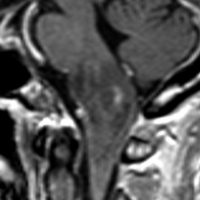

diffuse, infiltrative びまん性のもの

染み込むように左前頭側頭葉から島回に広がるAAです。T2/フレア像でにじむように広がり,ガドリニウム増強されません。グレード 2 (びまん性星細胞腫)と区別が難しいものです。

もちろん手術摘出できないもので,生検手術のみを行います。この大きさのものに60グレイの放射線治療をすれば高度の認知機能低下は避けられませんから,患者さんと照射線量をよくよく相談します。でもAAは放射線化学療法で長期生存が望めます。50-54グレイの線量が選択されます。